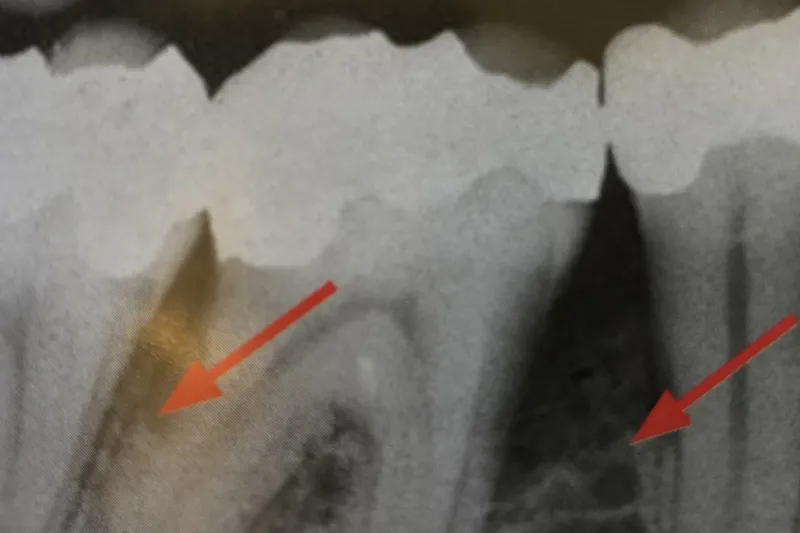

I undersøgelsen indgik 264 patienter, som havde mindst 20 pocher > 4 mm og mindst 30 % marginalt knoglesvind. 133 af dem fik intensiv parodontalbehandling med mundhygiejneinstruktion, subgingival rensning under lokalanalgesi, indiceret kirurgisk behandling og efterfølgende kontrol og indiceret reinstruktion og rensning hver 3. måned igennem et år. En kontrolgruppe med 131 patienter fik supragingival rensning og afpudsning med samme intervaller som i gruppen med intensiv behandling. Begge grupper fik foretaget nødvendige ekstraktioner inden forsøgsperiodens start, og patienterne i kontrolgruppen fik indiceret intensiv behandling efter forsøgsperiodens udløb.